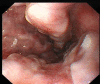

Background: Esophagogastric variceal bleeding (EGVB) is a potentially life-threatening complication of portal hypertension. Endoscopic treatment combined with pharmacotherapy remains the mainstay in the management of acute variceal bleeding.

Results: A total of 85 questionnaires were collected. There was no statistical difference in the selection of items (P < .05 indicated statistical significance). The majority of endoscopists (95.29%) offered EGV screening for patients with liver cirrhosis. The location, diameter, and risk factor classification was selected by 82.35% of endoscopists. Endoscopy + medication was preferred (42.35%) for the primary prophylaxis of moderate-to-severe EGVs. There was no statistical difference in emergency intervention time for active EGVB (P > .05). The response "patients receive emergency endoscopic intervention within 12 hours" was selected by 61.2% of the endoscopists. The preferred emergency treatment for EGVB was combination treatment (40%). Tissue adhesive embolization was selected for the treatment of gastric variceal bleeding by 74.12% of endoscopists; transjugular intrahepatic portosystemic stent shunt/percutaneous transhepatic variceal embolization were selected as remedial measures by 48.23% to 52.94% of endoscopists. In addition, 67.06% of endoscopists elected to perform secondary prophylaxis and treatment within 1 week after hemostasis. Endoscopy and endoscopy + medication were selected by 44.71% and 49.41% of endoscopists, respectively, for secondary prophylaxis. The choice of laboratory indicators did not differ with length of experience.